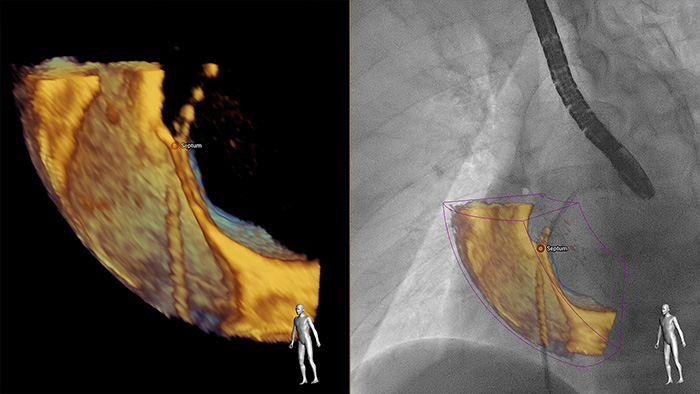

Maior perceção e confiança na procura e tratamento do problema através do SmartFusion. O EchoNavigator funde automaticamente os raios X e a ETE 3D em tempo real, para que possa guiar o dispositivo de forma intuitiva no espaço 3D mais rapidamente.